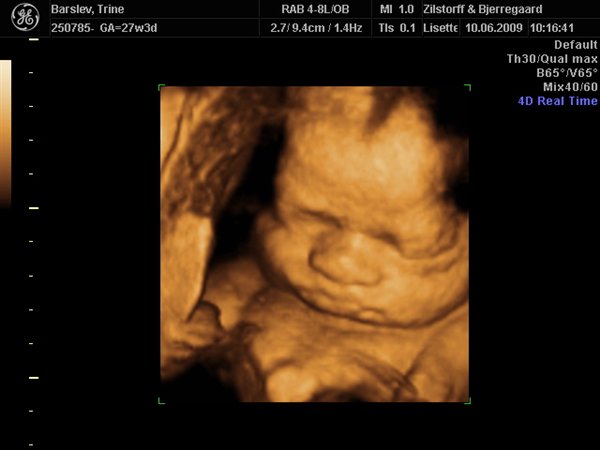

Hjemvendt fra 3D-scanning (Billedspam)

Fandt lige det her af Stella da hun er 3 mdr. og laver Artomund og basun-kinder som han også gjorde på et tidspunkt..

Måske er der en lille lighed alligevel

Vedhæftede fotos (klik for at se i fuld størrelse)

vildt nok man kan se dem så tydeligt på 3D, hva!?

Nåehhhh, hvor er det vildt hvad man kan se på sådan en 3d scan.....

Hvem har lavet den 3d-scanning, for synes godt nok det er nogle fine billeder? Meget tydelige.

Det har de hos Zilstorff og Bjerregaard i Silkeborg (www.scanningsjordemoderen.dk)

Det er virkelig den bedste service man får der og er super glad for billedkvaliteten